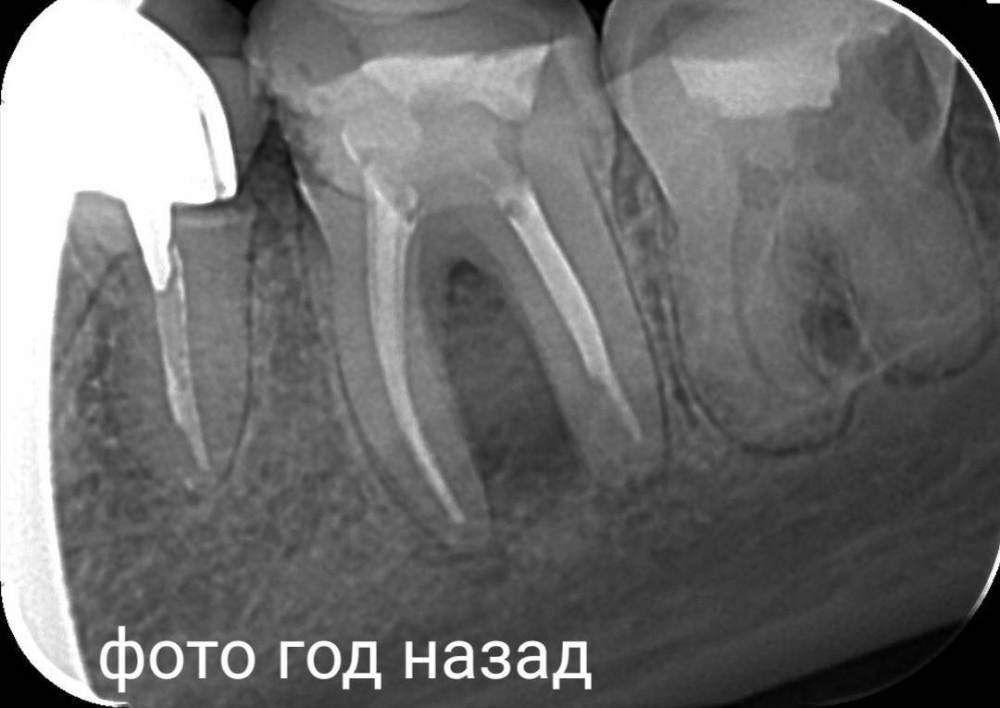

Chelovek2012 Опубликовано 20 апреля, 2023 Автор Поделиться Опубликовано 20 апреля, 2023 Вот рентген, год назад Мне 38 лет Ссылка на комментарий

IvanK Опубликовано 21 апреля, 2023 Поделиться Опубликовано 21 апреля, 2023 Здравствуйте, год - это уже срок, не очень актуально, но, исходя из этого снимка, я бы рекомендовал: проверить контактный пункт 15-16, состояние пломб 11,12, на 25 возможно кариес под коронкой 15, 26, 37 оценить по дкт корни, далее протезирование 36 кариес под коронкой оценка контактных пунктов 45-46-47 1 Ссылка на комментарий